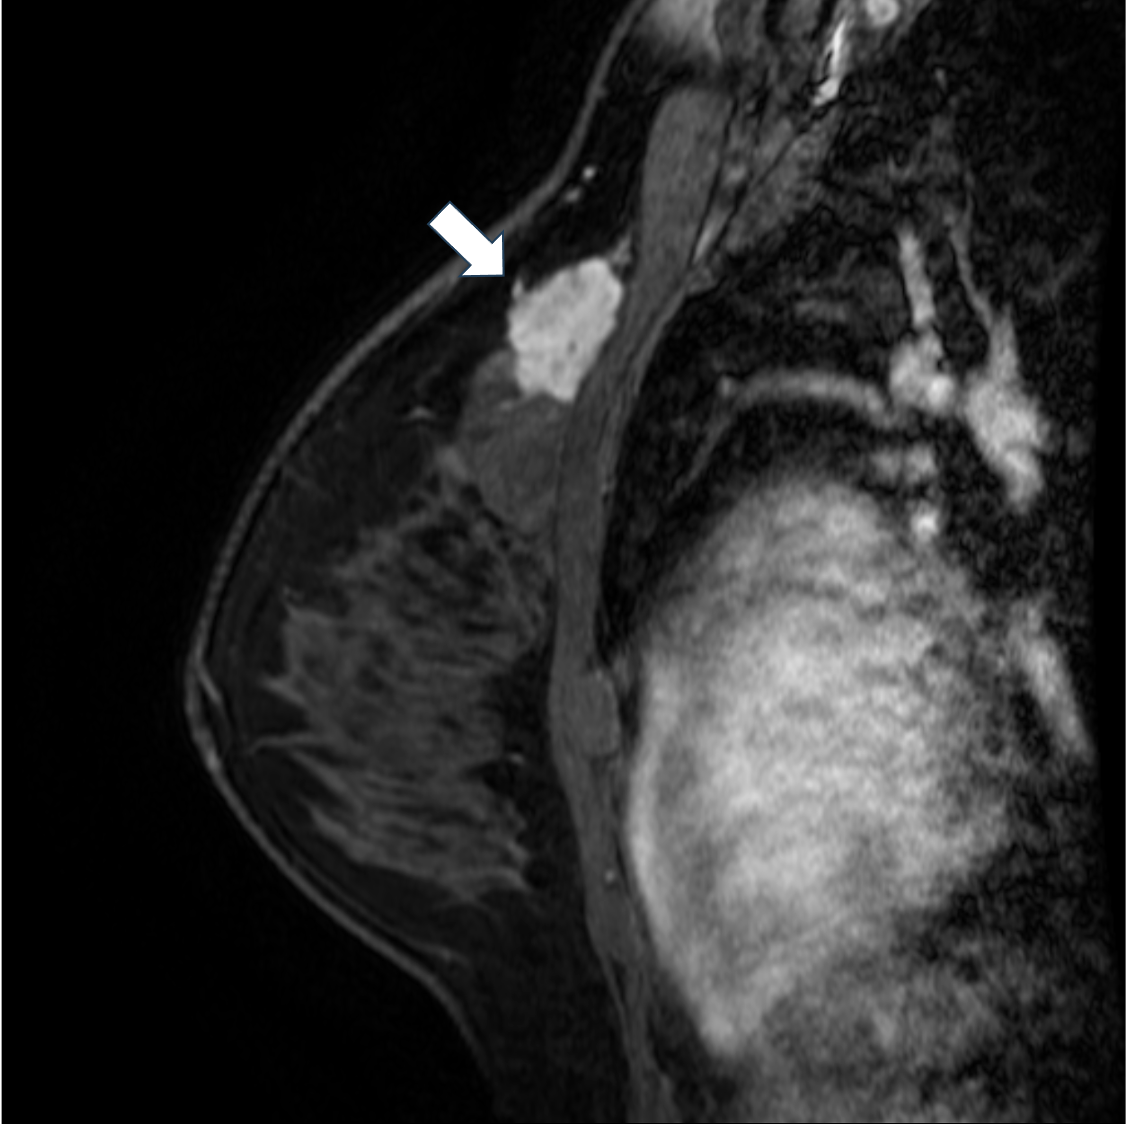

7. 造影後高分解能T1強調画像

造影後高分解能T1強調画像は不整な腫瘤の形状や不均一な内部構造が明瞭に描出されている。